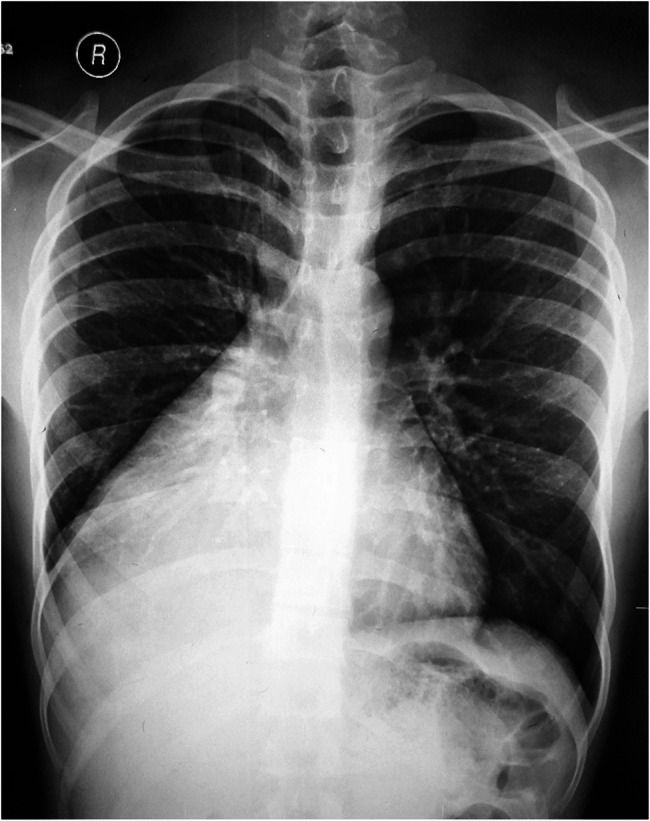

Case presentation: A 22-year-old university student was incidentally noted to have abnormal findings on cardiorespiratory examination. A chest X-ray suggested dextrocardia with cardiomegaly, but further imaging revealed a large anterior mediastinal mass. Contrast-enhanced computed tomography (CT) of the chest showed a well-encapsulated, predominantly fat-density mass (approximately 24 × 15 × 12 cm) in the anterior mediastinum extending into the right hemithorax without invasion of adjacent structures. The lesion caused rightward mediastinal widening but no actual cardiac enlargement, dextroposition or lung collapse. Surgical resection via right mini-thoracotomy was performed. The Gross examination revealed a large, lobulated, encapsulated tumour with a yellow, fatty cut surface and interspersed solid areas. Histopathology confirmed the presence of mature adipose tissue with thymic lobules (cortex, medulla, and Hassall's corpuscles), consistent with thymolipoma, showing no evidence of malignancy. The patient's postoperative recovery was uneventful, and the heart resumed its normal anatomical position.